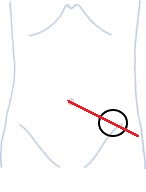

体表だとヘソと上前腸骨棘(赤丸)とを結んだ線(赤線)の真ん中やや外側あたり(黒丸)です。

この黒丸部分がS状結腸です。

この辺りで硬くなっている部位を探してマッサージを行ってください。

少し痛いと思いますがしっかりほぐしてください。

この部位は腸しかないので安全です。